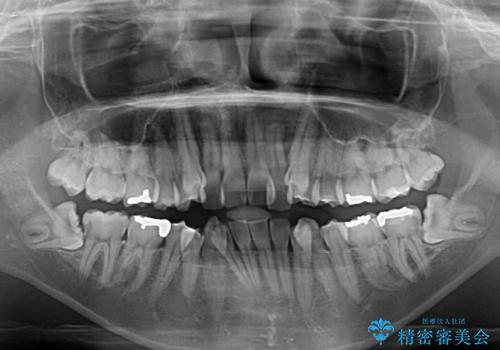

- 八重歯や前歯のデコボコを気にして来院された患者様です。

目立たない装置を希望されたので、上顎が裏側装置のハーフリンガルを選択し、上下左右の小臼歯(計4歯)を抜歯して矯正治療を行うこととしました。

補助装置を併用することで、八重歯を速やかに改善し、治療期間の短縮を図ることとしました。